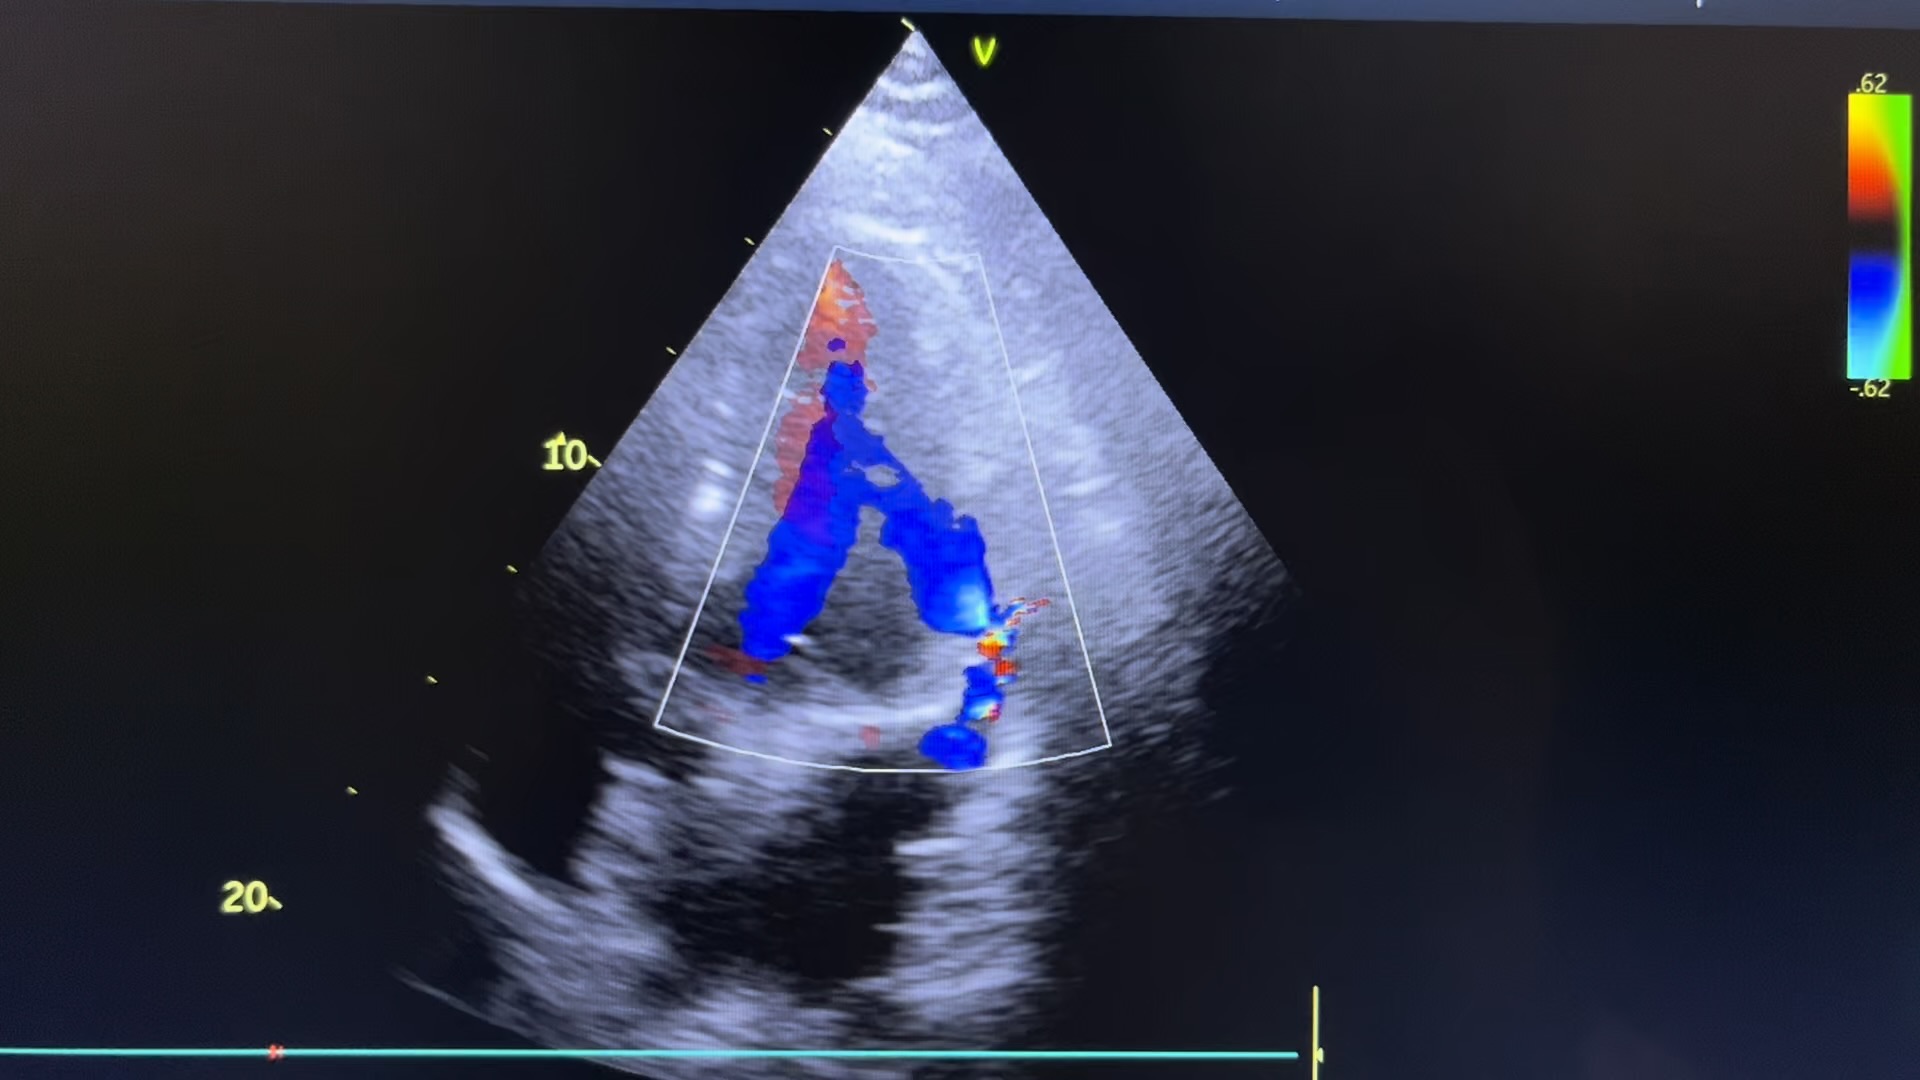

临床申请单上面无任何信息,看了床头牌才知道急性心梗入院,看左室长轴(可惜没拍图)心尖四腔心时都发现左房后外侧有一个囊性回声66✖️40mm左右,左房受压变得很小,一上彩,好家伙~穿孔了!询问值班医生,说心梗是广泛前壁,不符合啊,那多切面看吧,怎么看都是侧壁下后壁动的不行,侧壁基底段穿孔。

心尖四腔看到左室侧壁基底段异常血流

心尖四腔看到左室侧壁基底段穿孔处异常血流

很容易会把这个大血肿看成左房,前缘遮挡二尖瓣处,给人一种二尖瓣有问题的假象